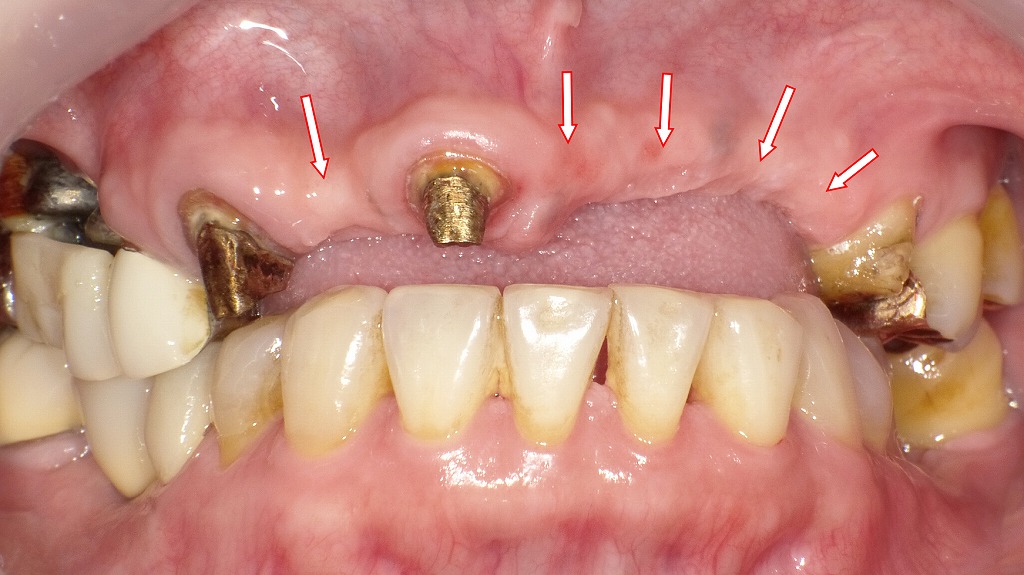

この画像は、右上3番から左上5番にかけて装着されていたブリッジを除去した状態を示しています。

前歯のブリッジを除去 🦷 現在の状態

- 支台歯:右上3番・右上1番・左上5番が残存しています。いずれも金属支台(メタルコア)が確認できます。

- 欠損部位:右上2番から左上4番までの広範囲が欠損し、矢印で示された歯槽頂部には明らかな陥凹と骨吸収がみられます。

- 粘膜の状態:ブリッジ下に長期間覆われていたため、歯槽頂部の粘膜はやや菲薄で、圧痕や陥凹を伴っています。

⚙️ 治療背景と問題点

- 右上3番〜左上5番の長大なブリッジは、支台歯が少なく力の負担が集中していました。

- 特に右上3番と左上5番の遠位支台への咬合力過重により、歯根破折や歯周支持組織の喪失のリスクが上がった可能性があります。

- 清掃不良や咬合不均衡も加わり、長期使用に伴ってブリッジ除去が必要となりました。

💡 今後の治療計画

- インプラント埋入予定部位:

- 右上2番

- 左上1番・2番・3番・4番

計5本のインプラントを予定しています。

- これにより、従来のように少数歯へ負担を集中させることなく、咬合力の分散と長期安定性の確保を目指します。

- また、骨吸収部位では骨造成(GBR)を併用することで、審美的・機能的な回復が期待されます。